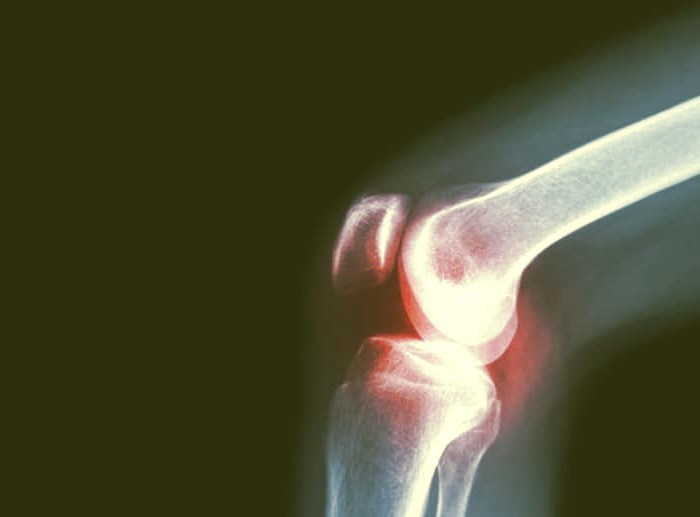

به شناسنامه تان نگاه کنید با بالا رفتن سن، مفصل زانو هم آسیب پذیرتر می شود. اما زمانی که افزایش سن با بیماری هایی مثل پوکی استخوان یا آرتریت همراه می شود، احتمال تخریب این مفصل بالا می روند و زانودرد و مشکلات هنگام راه رفتن و نشست و برخاست، همراه همیشگی فرد می شود.

مراقب آسیب های ناگهانی باشید صدمات ناگهانی، از شایع ترین دلایل آسیب دیدن زانوها هستند. وارد شدن ضربه مستقیم به زانو، پیچش غیرطبیعی، سقوط روی زانو، خم شدن غیرطبیعی و فشار آمدن به این مفصل و مواردی از این دست، احتمال ایجاد آسیب مزمن و مقاوم به درمان را بالا می برند. در چنین مواردی ممکن است در زانو یا ساق پایتان احساس بی حسی، ضعف یا سردی کنید و هنگام راه رفتن یا حرکت دادن این مفصل، صدایی را از زانوهایتان بشنوید. حال اگر این آسیب ها با کشیدگی، دررفتگی یا آسیب دیدگی رباط ها و تاندون ها که از زانو حمایت می کنند همراه شود، جبران آن دشوارتر می شود. گذشته از این پارگی مینیسک و آسیب دیدگی رباط ها، می تواند فرد را به درمان های تهاجمی نیازمند کند.